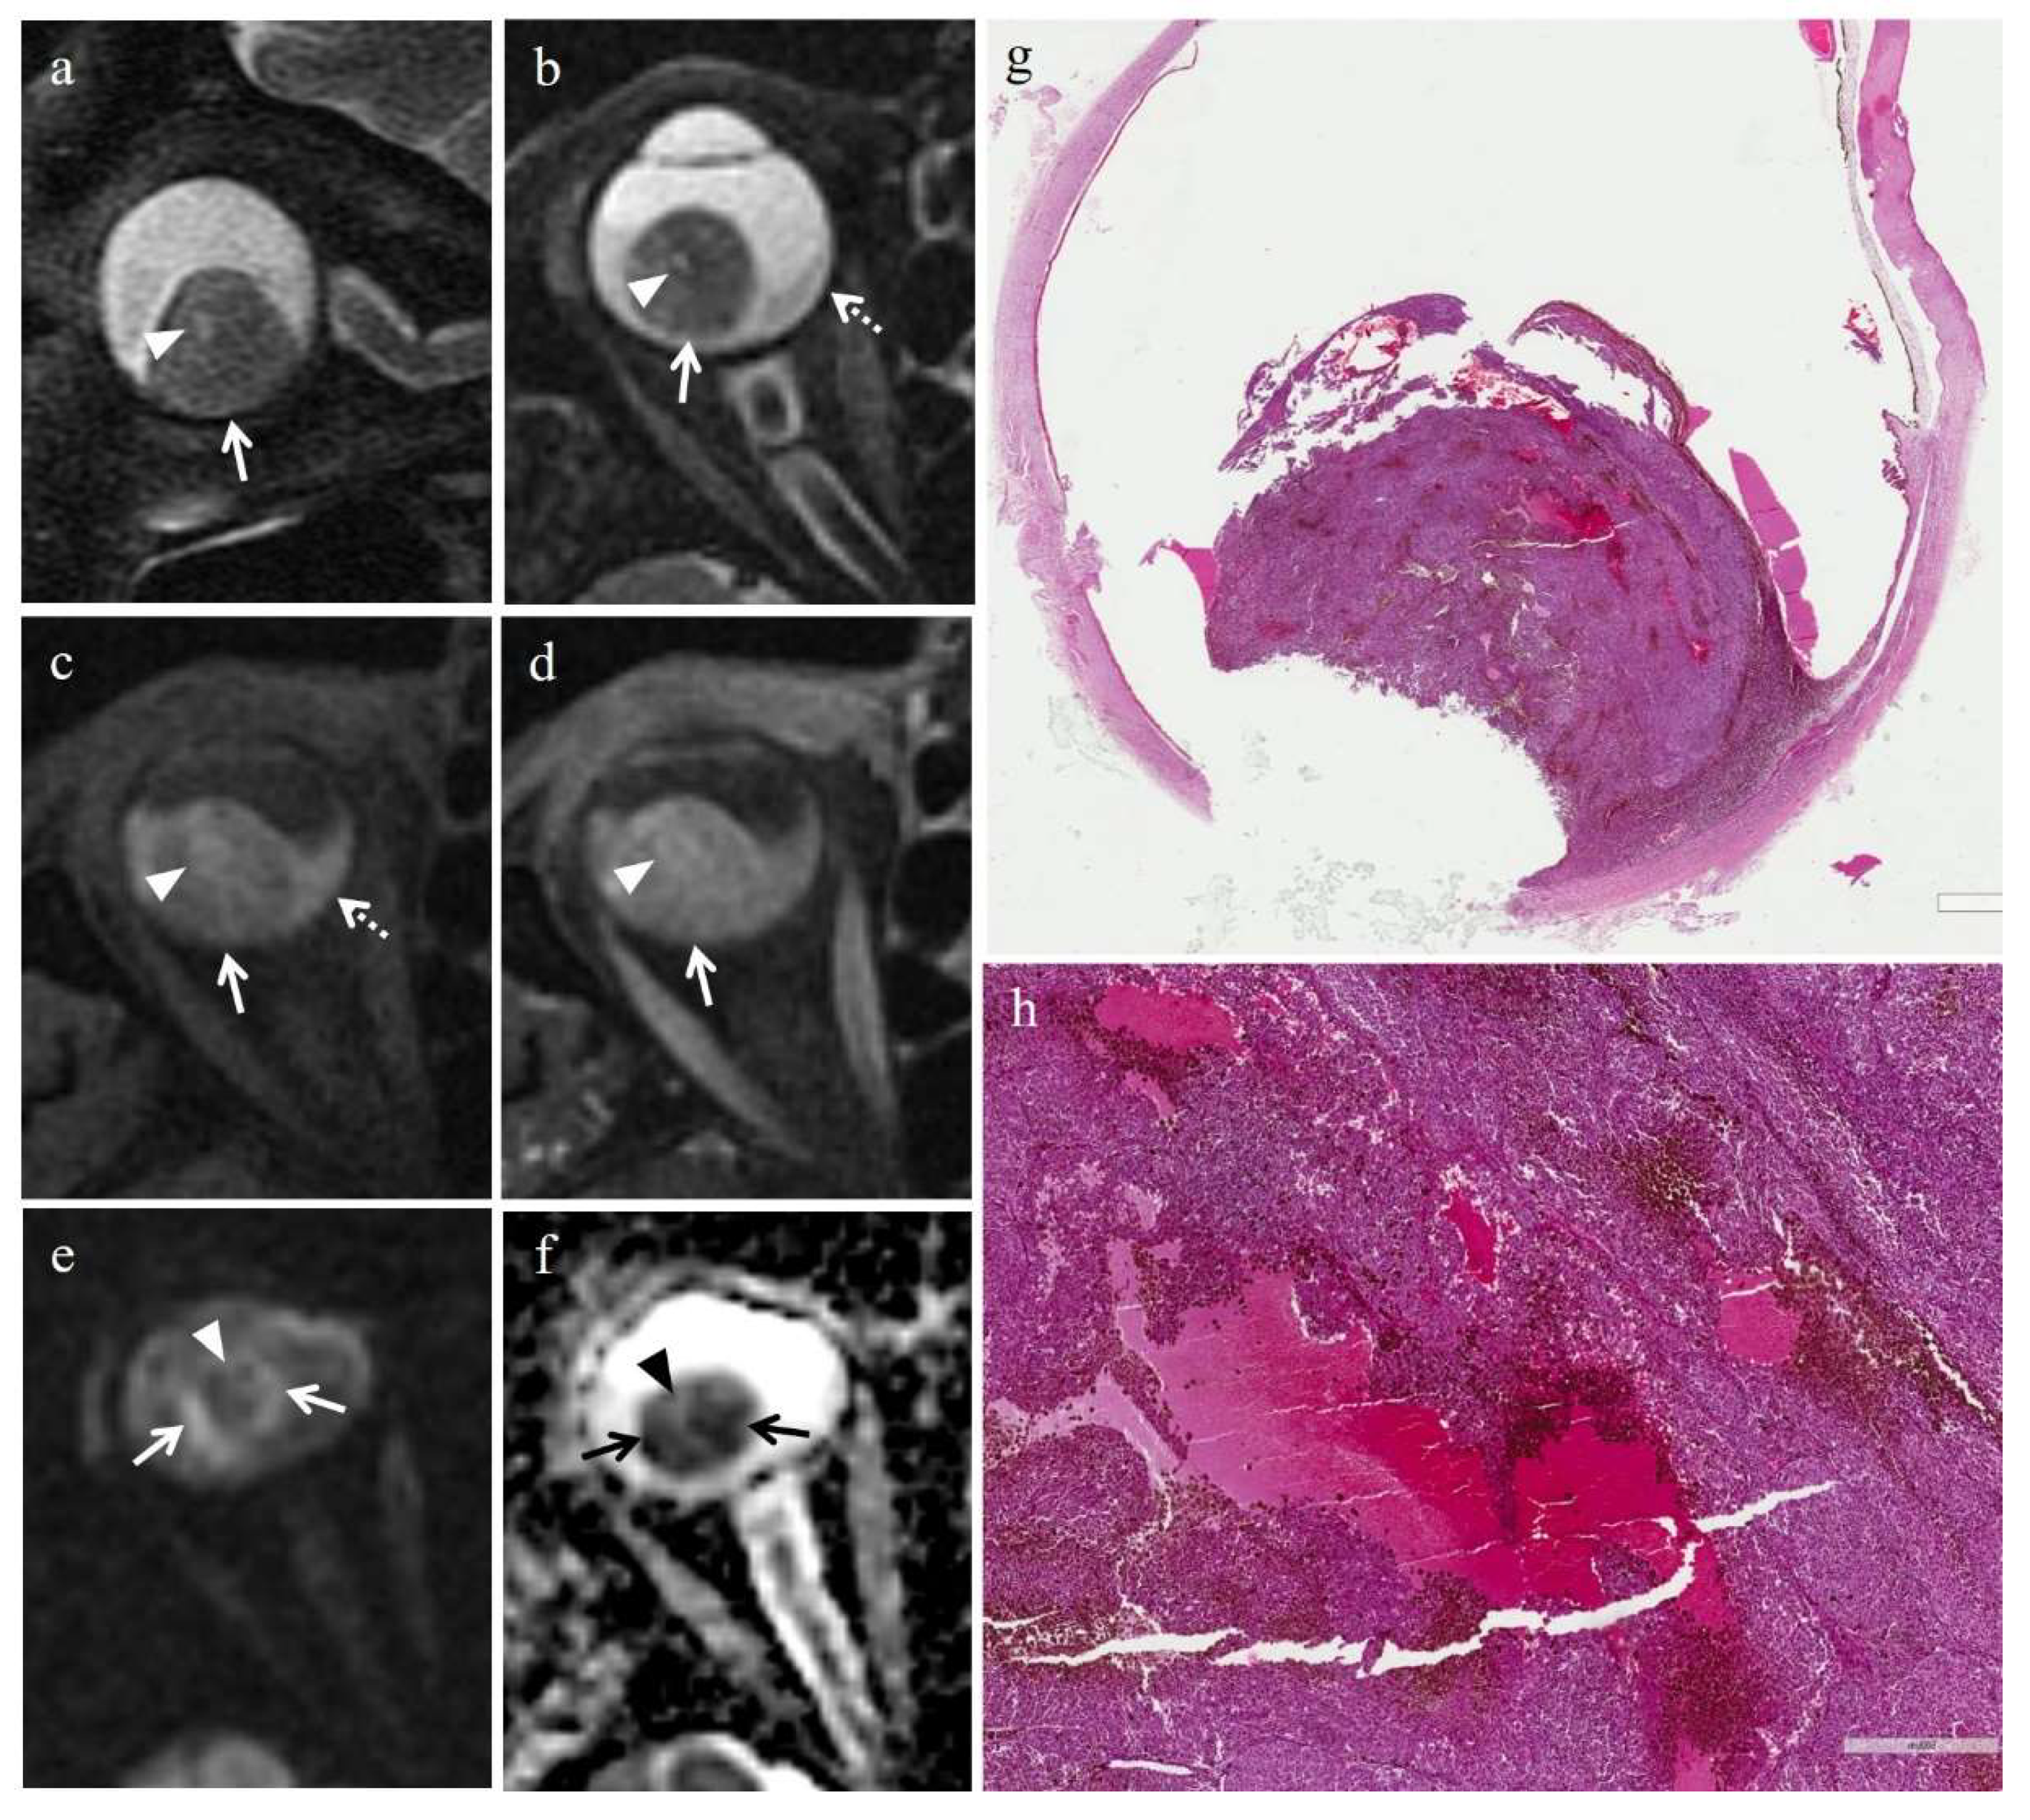

| Patient | Histologic Type | Degree of Pigmentation | Degree of Necrosis | Necrotic Pattern |

|---|---|---|---|---|

| 1 | Necrosis without viable tumor tissue | - | Grade III | Sharply demarcated tumor necrosis |

| 2 | Spindle cell | Pigmented | Grade I | Sharply demarcated tumor necrosis |

| 3 | Epithelioid cell | Pigmented | Grade II | Sharply demarcated tumor necrosis |

| 4 | Spindle cell | Pigmented | Grade III | Sharply demarcated tumor necrosis |

| 5 | Mixed cell type | Poorly pigmented | Grade I | Multiple foci- hemorrhagic/coagulative-type |

| 6 | Mixed cell type | Poorly pigmented | Grade III | Sharply demarcated tumor necrosis |

| 7 | Spindle cell | Poorly pigmented | Grade III | Sharply demarcated tumor necrosis |

no enhancement; M: melanoma; RIN: radiation induced necrosis.| Patient | T2 | T1 | Gd-T1 | DWI | ADC × 10−3 mm2/s ** |

|---|---|---|---|---|---|

| 1 | Hypointense | Hyperintense | No enhancement | No restriction | - |

| 2 | - | - | - | - | 0.76 |

| 3 | Hypointense | Hyperintense | No enhancement | No restriction | 0.84 |

| 4 | Hypointense | Hyperintense | No enhancement | No restriction | - |

| 5 | Hyperintense | Hypointense | No enhancement | No restriction | 0.67 |

| 6 | Hypointense | Hyperintense | No enhancement | No restriction | - |

| 7 | Hypointense | Hyperintense | No enhancement | No restriction | 0.86 |